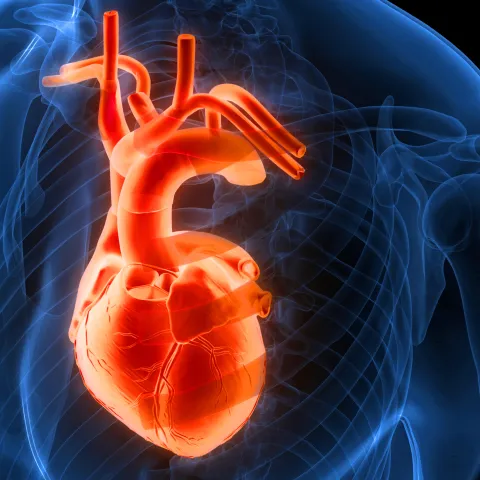

Obadah Al Chekakie, MD, is a cardiologist specializing in clinical cardiac electrophysiology. Read along as he answered questions related to atrial fibrillation procedures.

Understand the complex relationship between your heart and colon health.